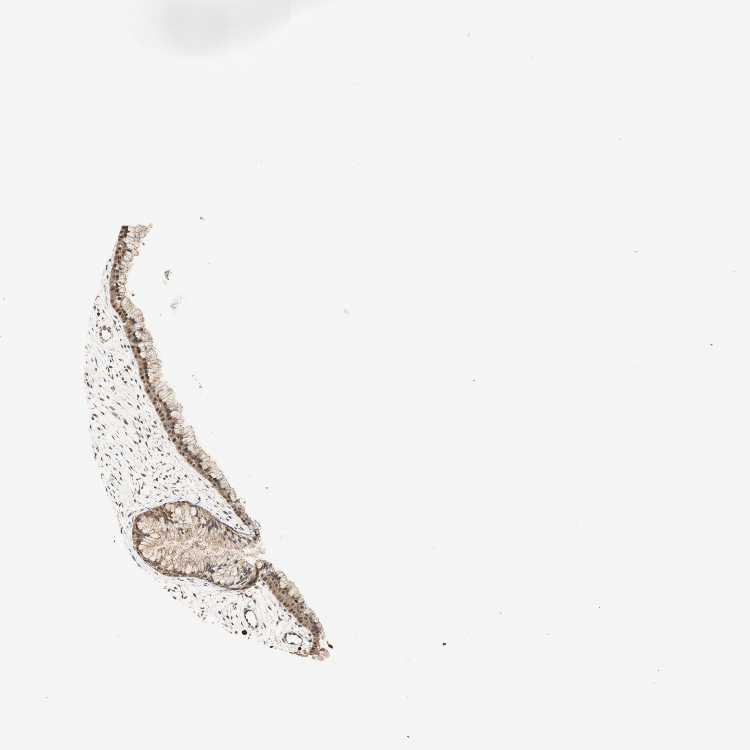

CERVIX - Antibody stainingi

Antibody staining in the annotated cell types in the current human tissue is reported as not detected, low, medium, or high, based on conventional immunohistochemistry profiling in selected tissues. This score is based on the combination of the staining intensity and fraction of stained cells.

Each image is clickable and will lead to virtual microscopy that enables deeper exploration of all samples and also displays staining intensity scores, fraction scores and subcellular localization as well as patient and tissue information for each sample.

Antibody HPA003150Antibody HPA018683

Glandular cells HighMedium

Squamous epithelial cells HighMedium